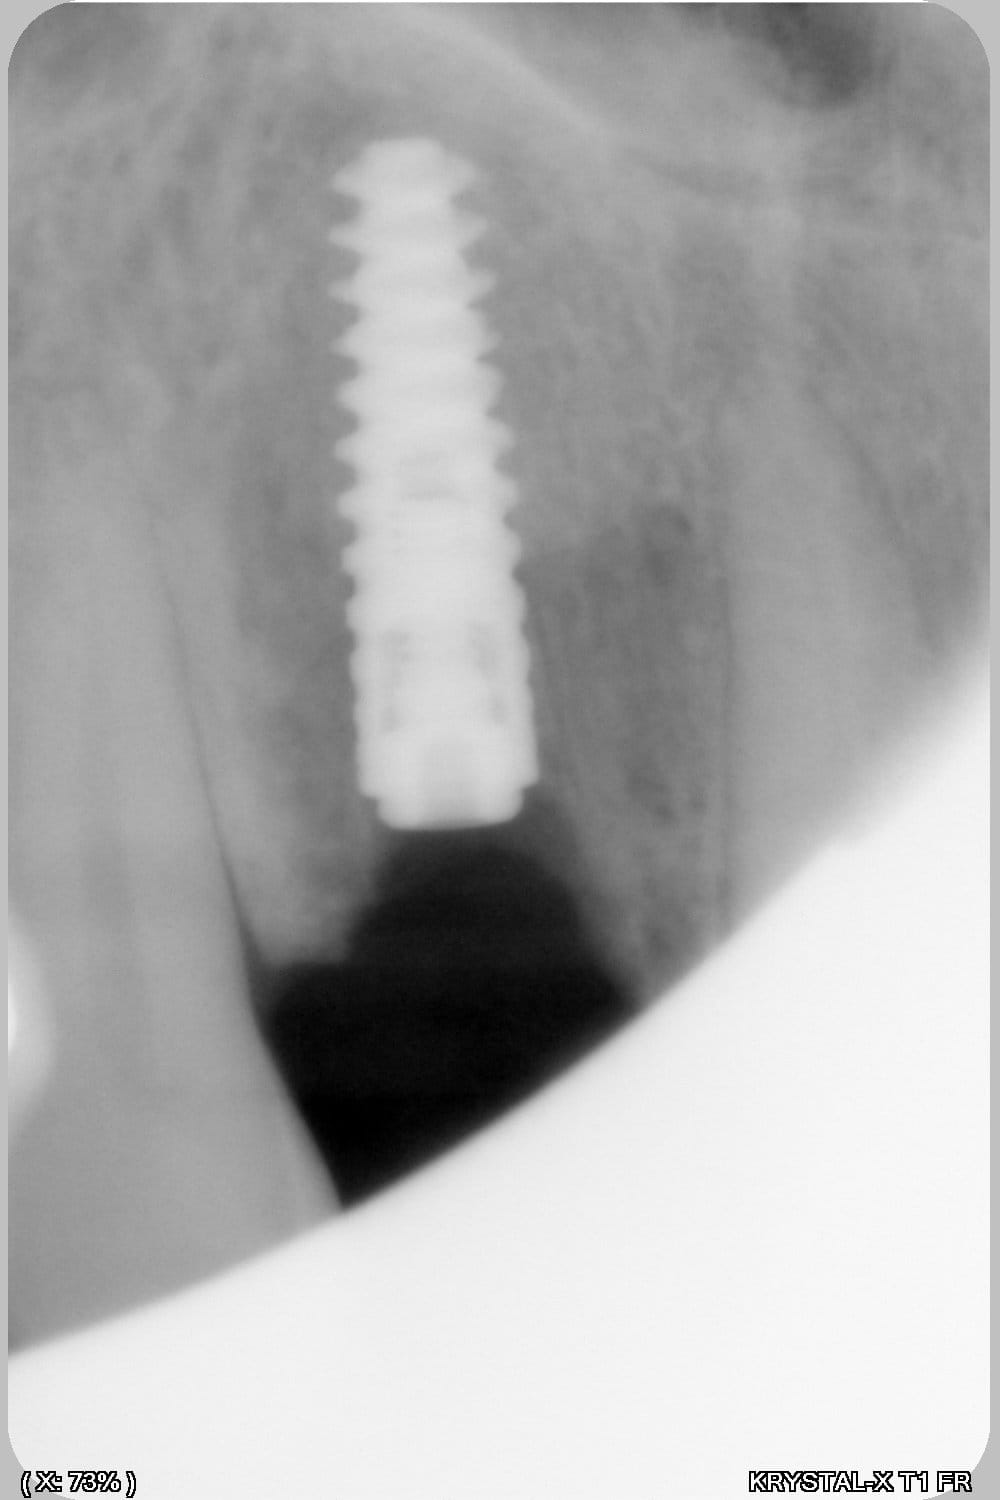

Thomas, tu as un plan pour guider dans un cas comme ça?

ou comment remplacer 12 avec soucis vestibulaire, par un implant, sans greffe, sans ROG, juste avec les mimines....?

Et bien pas de cone beam, pas de scanner,pas de panoramique...pour ne pas irradier l'os...et franchement je ne vois pas en quoi un guide me servirait dans un cas comme ça.